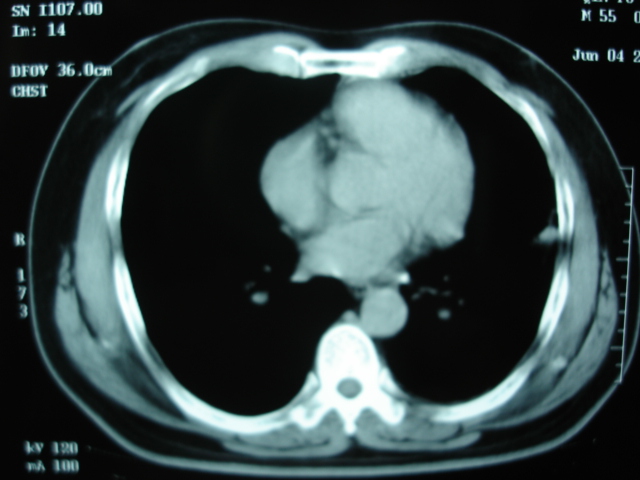

第二次ct2009.6.7 住院后ect未见异常,查痰(阴性)大量抗菌素抗炎一个月后病灶明显变小,7月5号出院后回家后口服抗菌素45天

第三次ct2009.8.21